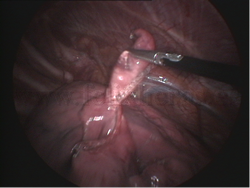

Exéresis de nódulos y metástasis